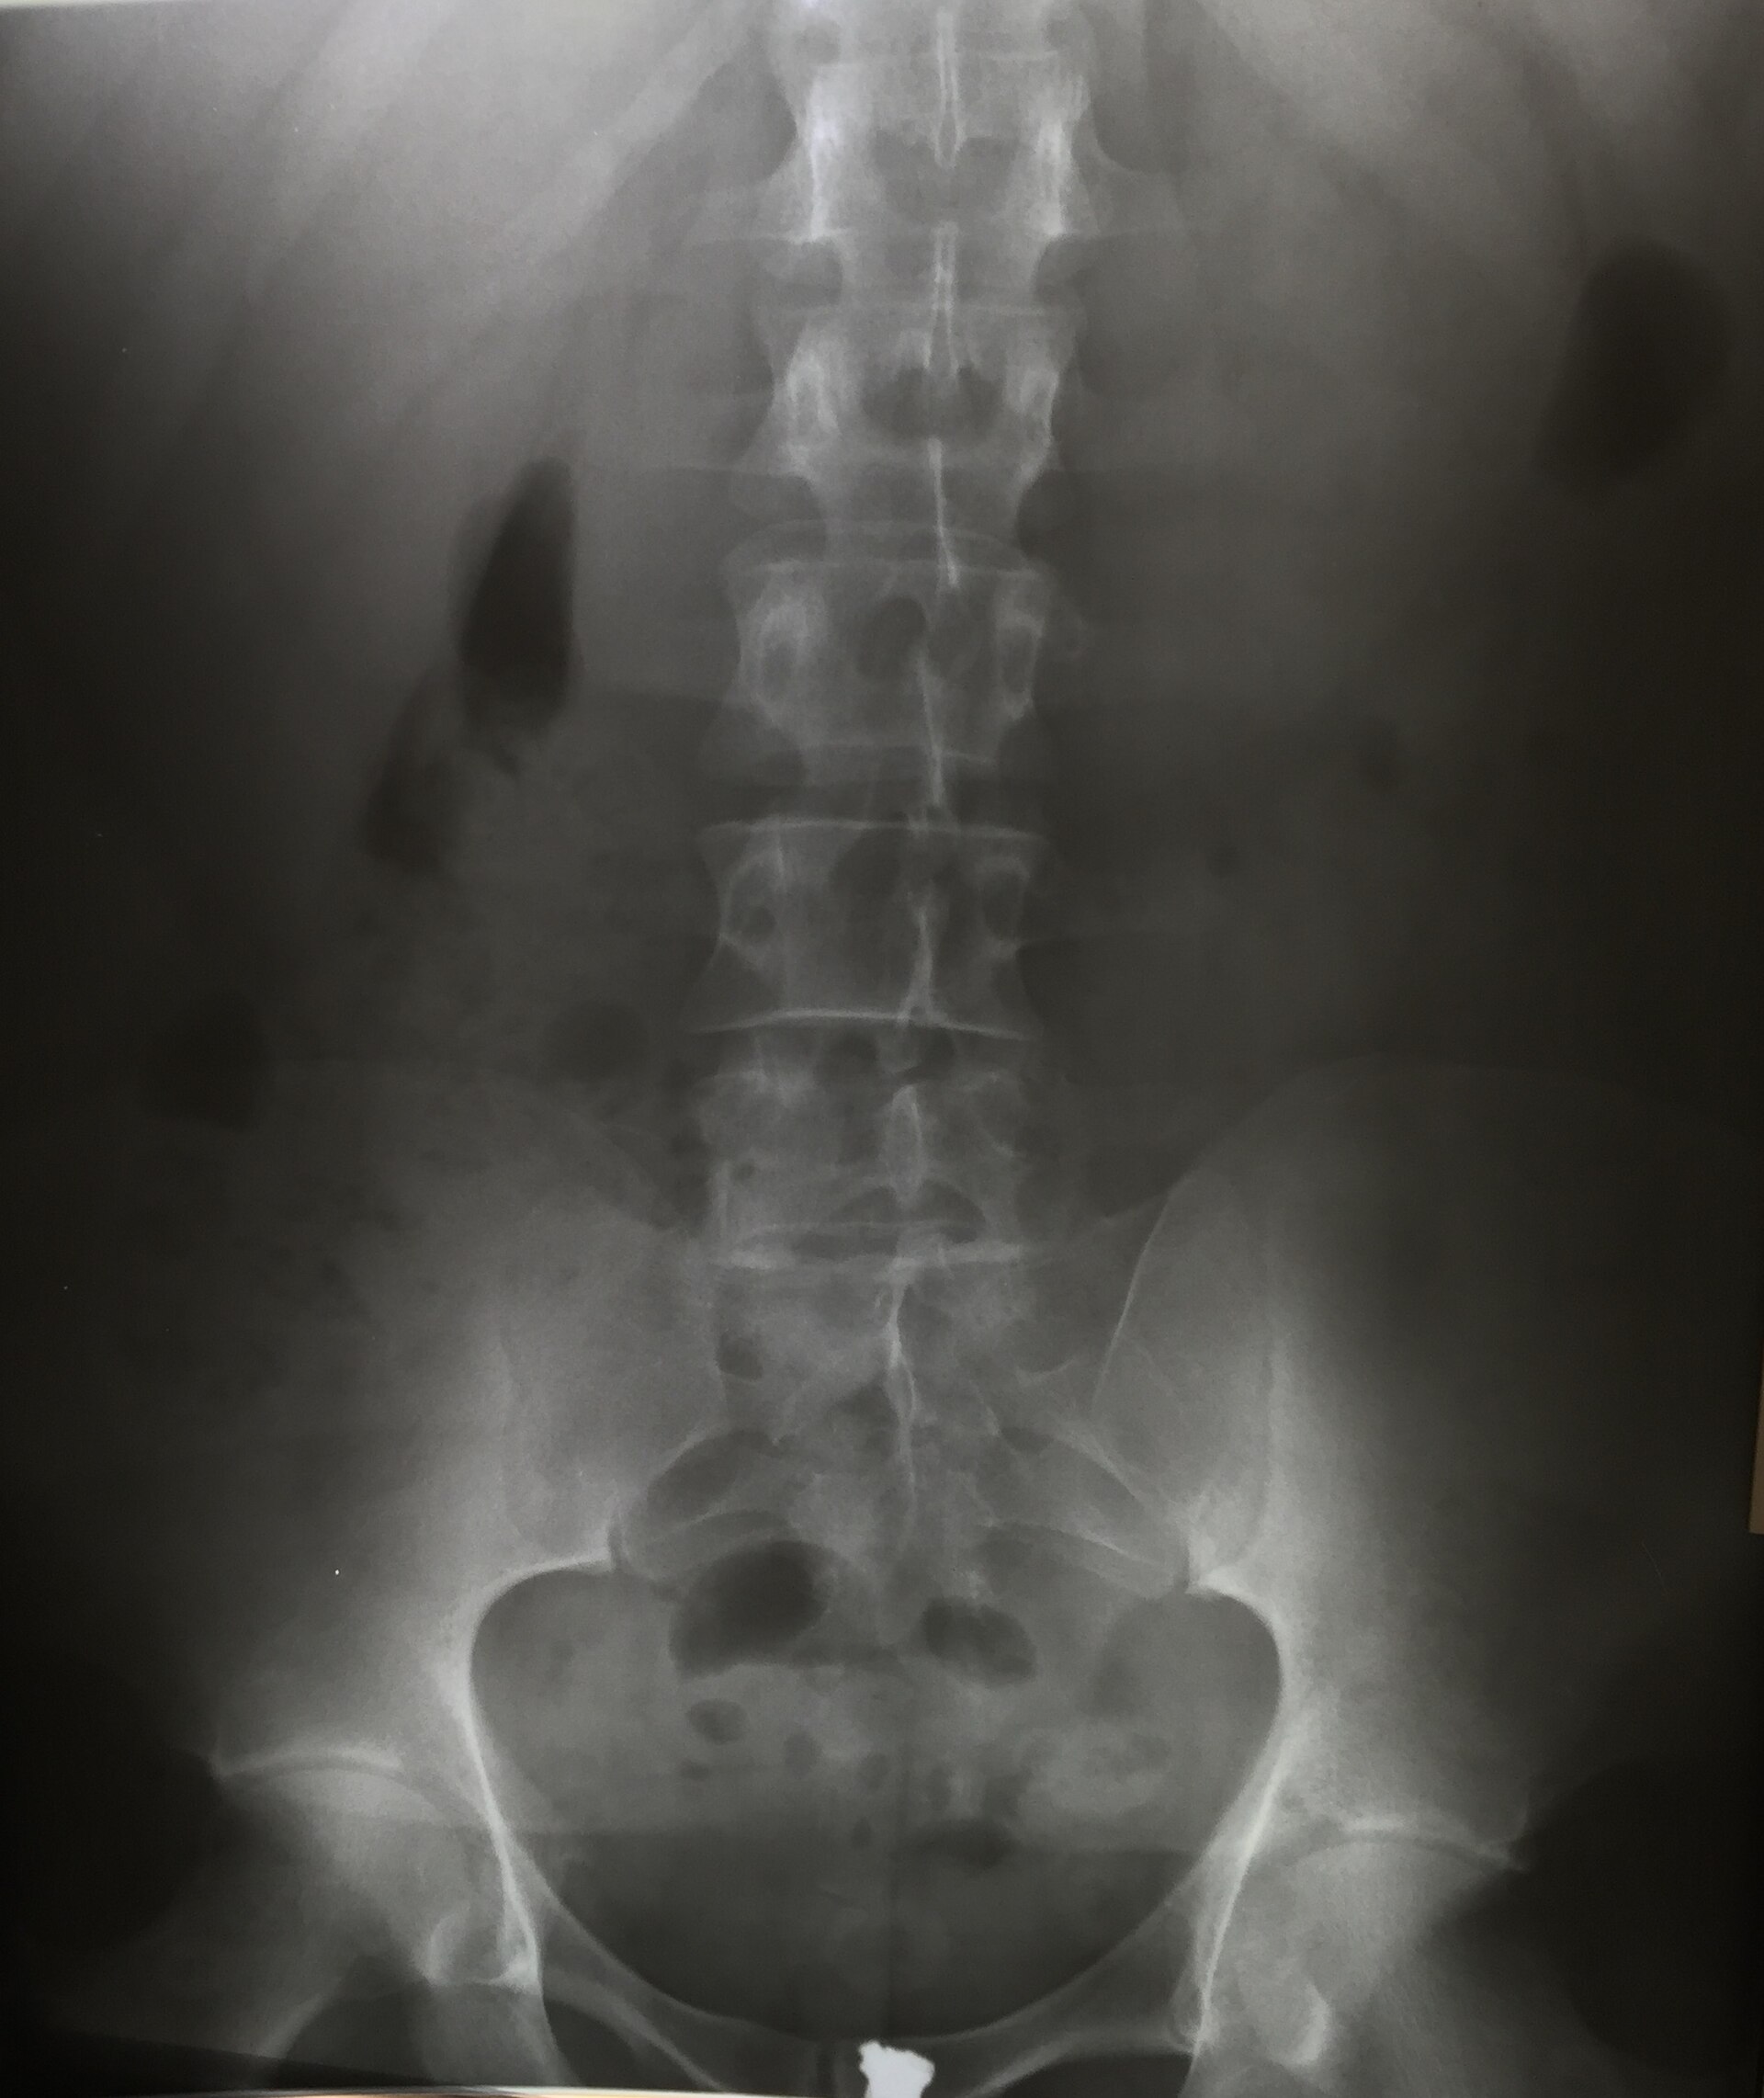

Anteroposterior radiograph of the lumbar spine.